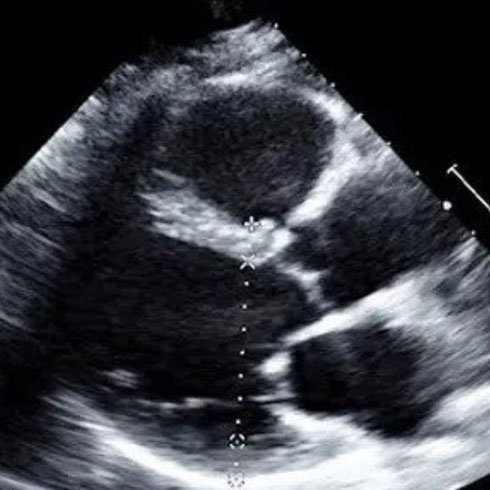

2D Echo